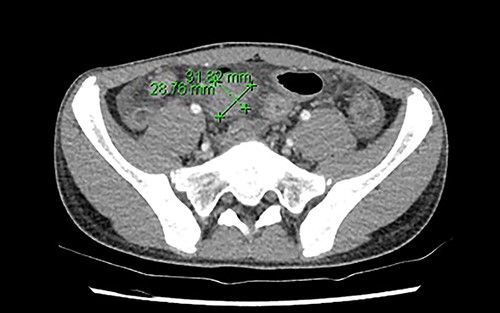

Initial blood investigations showed an elevated C-reactive protein (100), neutrophilia (8.51 × 109/L), raised ferritin (118ug/L), raised D-dimer (1.68 mg/L) and lymphopenia (1.17 × 109/L). His blood cultures were negative. Abdominal ultrasound found a thickened distal ileum with surrounding inflammatory phlegmon and possible microperforation. The appendix, however, appeared normal. Due to the unusual findings of the ultrasound and abnormal labaratory tests, he underwent an abdominal computed tomography (CT), which reported a long segment circumferential thickening of bowel wall involving ileocaecal valve to distal and terminal ileum. There was an associated area of phlegmon adjacent to the mesentery measuring 29 × 32mm (Fig. 1). The overall investigations met the diagnostic features for PIMS-TS as per guidelines from the Royal College of Paediatrics and Child Health (Table 1) [1].

The region of phlegmon in the adjacent ileal mesentery, measuring about 29 × 32 mm.